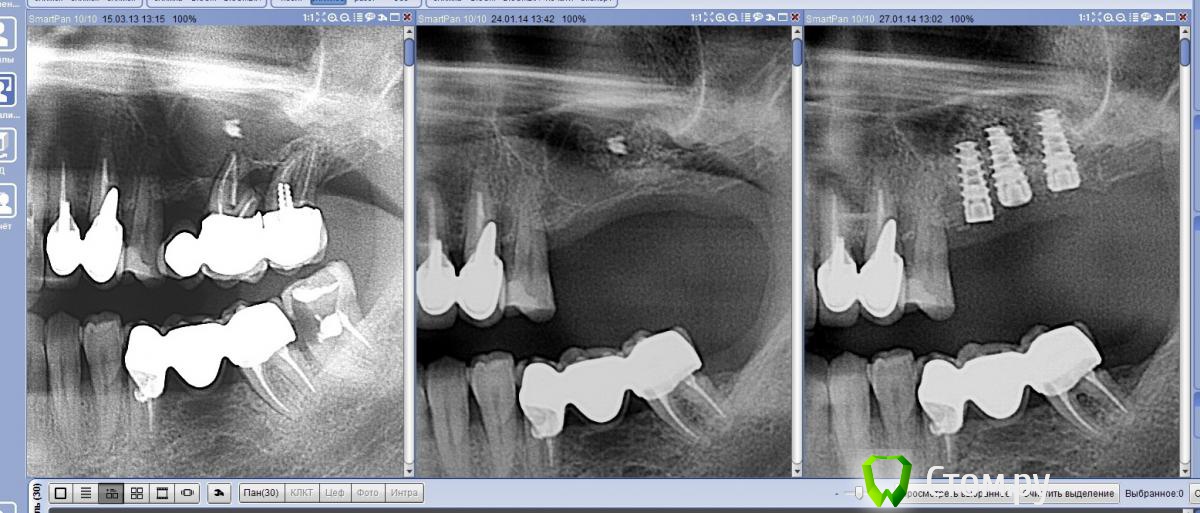

Andex Опубликовано 7 октября, 2014 Автор Поделиться Опубликовано 7 октября, 2014 Да, совсем забыл про продолжение. Я в итоге сделал повторный ре-синус (закрытый) - знаю что кто-то сделал бы по-другому, но я сделал так,как хотел. Импланты уже 6 мес стоят под нагрузкой, наблюдаю дальше. Ссылка на комментарий

Andex Опубликовано 8 октября, 2014 Автор Поделиться Опубликовано 8 октября, 2014 Спасибо за информацию. Если позволите, пара вопросов. Имплантаты стоят в позиции 25, 26, 27? Если да, то как ведёт себя кость между 25 и 26; есть ли свежие снимки?Да, 25,26,27. Кость между 25 и 26 - я не знаю как ведет, на снимке через пол года нагрузки она в том же состоянии, что и после операции. Расстояние между 25 и 26 в реальности больше, чем на панораме, тк рентгенолог не совсем удачно позиционировала голову пациента. Ссылка на комментарий